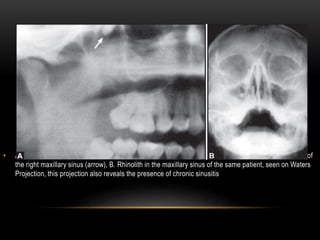

• Antrolith (stone in maxillary sinus) on the floor of the sinus.

• It is asymptomatic.

• A. Rhinolith in the maxillary sinus, seen on an OPG. The rhinolith is seen located at the posterior wall of

the right maxillary sinus (arrow), B. Rhinolith in the maxillary sinus of the same patient, seen on Waters

Projection, this projection also reveals the presence of chronic sinusitis